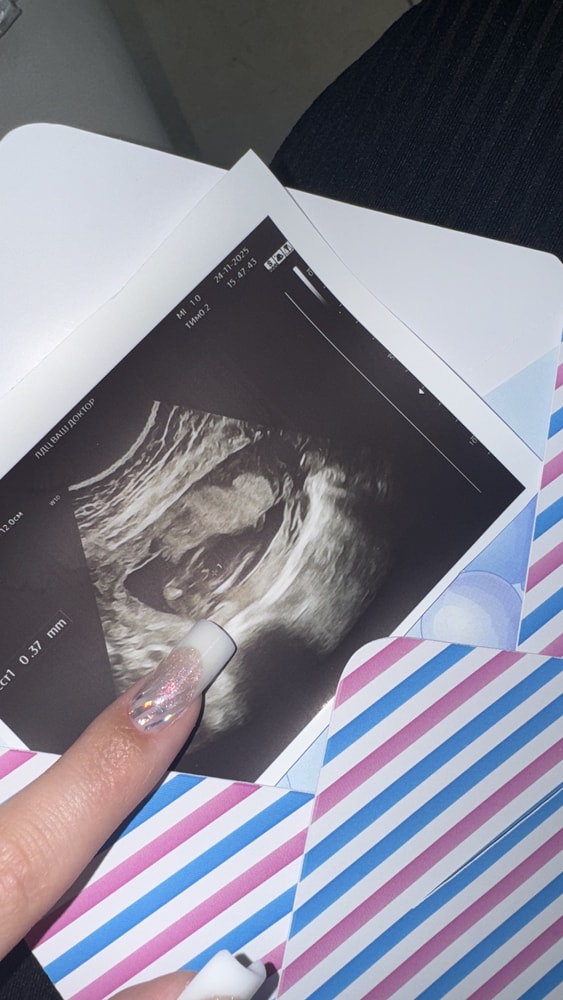

УЗИ ПОЛ В 16 недель

УЗИ, КТГ, доплерДевочки, на скрининге предложили девочку , ходила все эти недели думая , что там девченка, а по фото в 16+3 нашли писюнчик🤣🤣🤣

Ваше мнение,это точно пацан или все таки пока непонятно?

Netta, вот у меня у кумы в 17 недель такая же фотка 😅 наш видимо растет еще , но я уже смирилась,раз нашли отросток,значит пацанчик🥹🤣